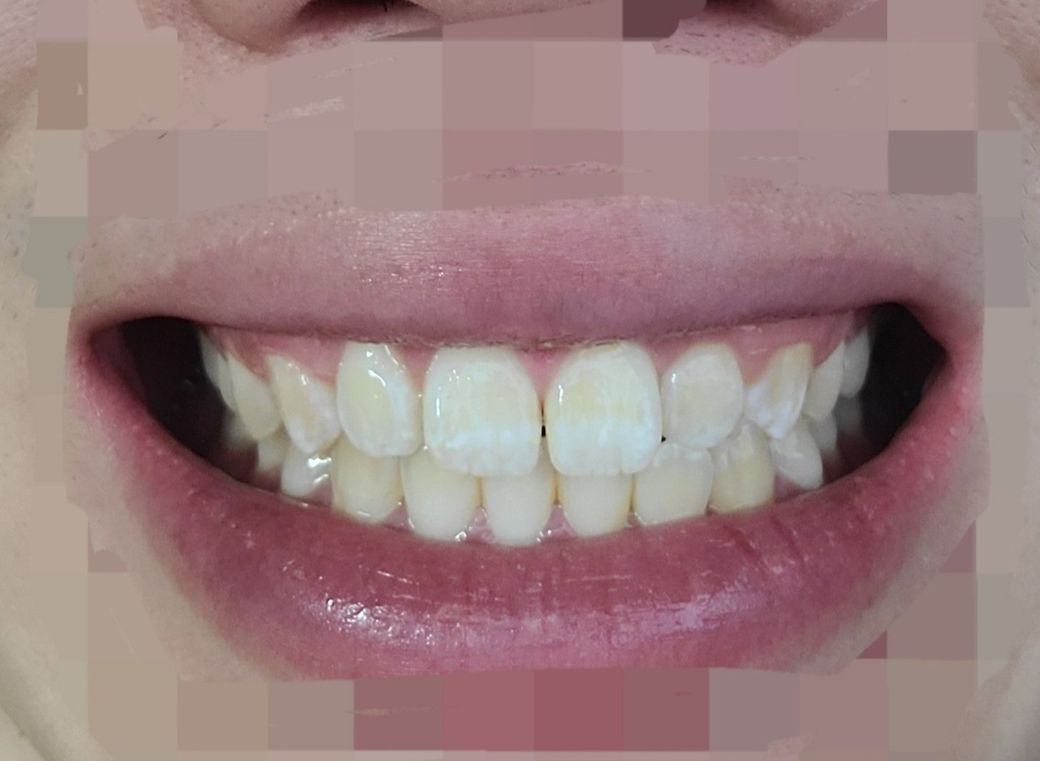

치아 어금니물리는게 오른쪽보다 왼쪽이 좀더 깊게 물리는 느낌이에요

치아 어금니물리는게 오른쪽보다 왼쪽이 좀더 깊게

물리는 느낌 약간틀어져서 그런느낌인데 교정하는게 좋을지 알고싶고요?

중심선이 안맞는 이유가 턱이 틀어져서인가요?

교합이 안좋은가요?

턱 비대칭여부 알고싶어요?

가끔 앞니쪽 윗니 측절치 잇몸이 아픈데 치아 위아래 부딪혀서 그런건가요?

앞니치아표면에 흰색으로 변색되어 있는데 이게 뭔가요? 양치문제인가요?

• 1번 째 사진

-> white spot이라고해서 탈회된 것인데 양치질이 부족해서 생기거나 어릴때 법랑질이 미성숙되어 생기곤합니다. 양치질 관리 잘해주시면 되겠습니다.

• 치아의 하얀 착색은 불소성분의 침착, 치태관리 미흡으로 인한 탈회 등의 원인이 있습니다.